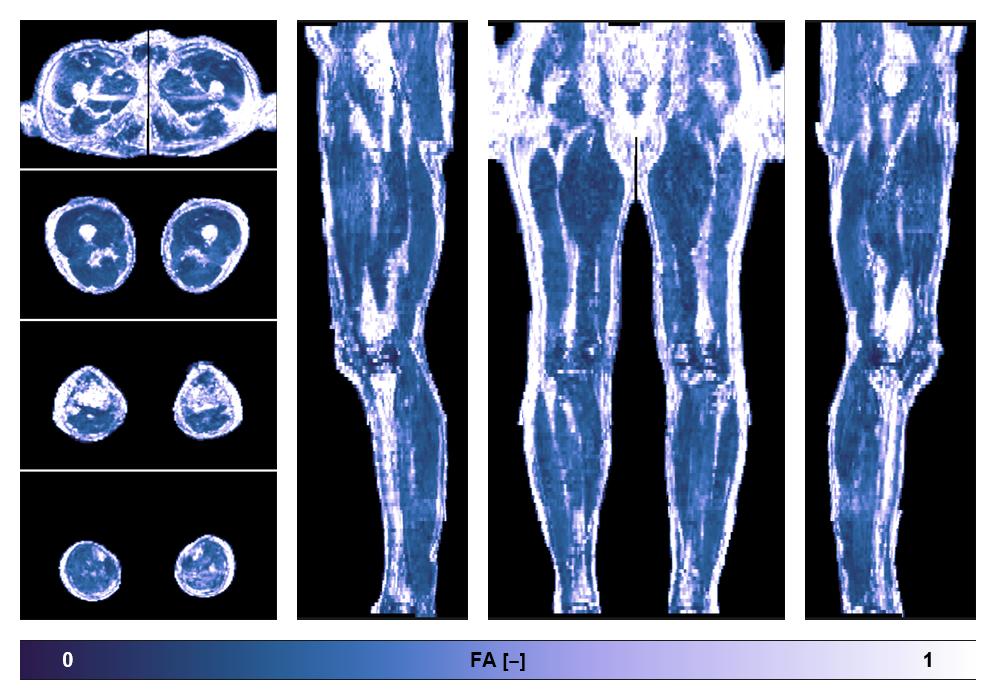

• Fractional anisotropy

IVIM corrected whole leg muscle fractional anisotropy obtained from diffusion tensor imaging.